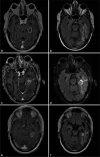

Background: Laser interstitial thermal therapy (LITT) is a minimally invasive surgical treatment for multiple intracranial pathologies that are of growing interest to neurosurgeons and their patients and is emerging as an effective alternative to standard of care open surgery in the neurosurgical armamentarium. This option was initially considered for those patients with medical comorbidities and lesion-specific characteristics that confer excessively high risk for resection through a standard craniotomy approach but indications are changing.

Results: This review provides an update of the relevant literature regarding application of LITT in neurosurgical oncology for the treatment of de novo and recurrent primary gliomas and brain metastases radiographically regrowing after previous irradiation as recurrent tumor or RN. In addition, this review details the limited experience of LITT with meningiomas and symptomatic peritumoral edema after radiosurgery. The advantages and disadvantages, indications, and comparisons to standard of care treatments such as craniotomy for open surgical resection are discussed for each pathology. Finally, the literature on cost-benefit analyses for LITT are reviewed.